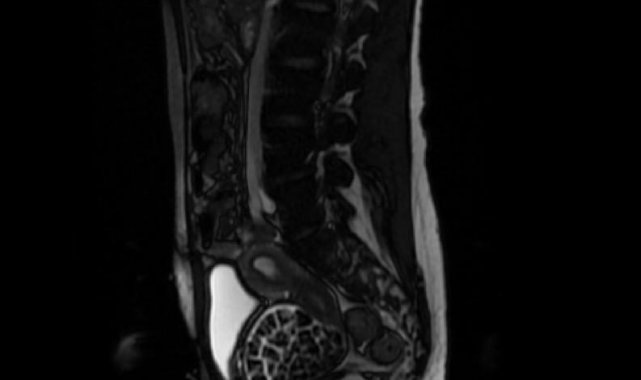

Hastasının durumuna yönelik konuşan Üroloji Uzmanı Doç. Dr. Erkan Erkan, "Hastamızın 2004 yılında doğduğunu ardından doğar doğmaz ekstrofi vezika dediğimiz 50 binde bir görülen bir anomaliden dolayı art arda ameliyatlar geçirdiğini öğrendik. 10 yaşında yine bir ameliyat geçirmişti, gerekli görüntüleme ve tetkiklerimizi yaptırdık. Normalde mesanesinin olması gereken yerin hemen arka kısmında taşlarla dolu bir kese olduğunu gördük, bunun üzerine ek görüntülemeler; MR çektirdik. Hastamız çelişkili açıklamalar almıştı, kendi radyolojik kliniğimiz ve edindiğimiz konsültasyonlarda taşların mesanede değil vajinal boşlukta oluştuğunu düşündük, bir planlama yaptık. Kadın doğum hocamızın da çabasıyla taşları tamamen temizledik ardından ileride normal bir hayat sürmesi bakımından oraya plastik cerrahi yaptık. 287 adet taş çıkardık, pratikte gerçekten görünce çok şaşırdık çünkü bu aynı zamanda literatürde çok nadir görülen bir olay. Biz ameliyata hazırlanırken de teorik olarak biraz araştırdık. Literatürde gördüğümüz kadarıyla buna benzer bu tanıma uyan bir vaka vardı. Literatürde sanırım yayınlanmış 2'nci vaka olacak. Farkındalık çok önemli, bilinçli bir hastamız vardı. Doğumsal anomaliyle doğan çocuklarımızda ileride bunlara bağlı bazı sıkıntılar çıkabileceğinin öngörülmesi lazım. İlgili tedavilerini alsalar bile düzenli takiplere gelmeleri gerekiyor. İleride eğer dikkat etmezse ki zannetmiyorum, tekrarlayabilir. Bu rahatsızlık ekstrofi vezikal epispadias durumu çok nadir bir durum" dedi.

Genç kızın uzun süredir devam eden karın ağrısı olduğunu söyleyerek sözlerine başlayan Jinekolojik Onkoloji Uzmanı Op. Dr. Emin Erhan Dönmez, "Mesane taşları olduğu düşünülerek daha büyük bir hastaneye refere edilmiş. Aramızda mini bir konsey yaparak muayene ettik. Vajen bir hazne görevi görerek orada durağan bir idrar, uzun süre beklediği için idrar içindeki minerallerde çökerek taşlar oluşmuş. Mesanedeki idrarın vajene akmış olabileceği ve vajende göllenen idrar nedeniyle taşların burada oluşacağını düşündük, ameliyatımızı planladık. Ameliyata tanı amaçlı girmiştik, sistoskopi (Mesane gibi idrar yollarını kapsayan kısımlardaki rahatsızlıkların teşhis ve tedavisinde kullanılan endoskopik bir yöntem) dediğimiz ameliyatı Erkan Hocam ile birlikte gerçekleştirdik. Önce mesaneyi bir görüntüledik, mesane tabanına yaklaşık 2-3 cm'lik bir alandan vajene fistülize olduğunu gördük. Mesaneden vajene geçtiğimiz esnada tüm vajenin taşlarla dolu olduğunu gördük. Tanı amacıyla girdiğimiz ameliyatta her şey de olağan gittiği için tedaviye geçtik. Taşların çıkabileceği kadar bir genişlik sağladık. Daha sonra yaklaşık en büyüğü 2,5 cm boyutlarında olan, irili ufaklı 287 tane taşı ameliyat esnasında çıkarmış olduk. Taşların tekrarlamaması için idrarın göllenmemesi, en azından dışarıya rahatça boşalabilmesi için vajinal rekonstrüksiyonu sağladık. Ameliyatta da herhangi bir problem yaşamadık. Literatürü Erkan Hocam ile birlikte değerlendirmiştik. Primer olarak vajende birikmiş olan bu kadar çok sayıda taşla ilgili bir makale görmedik, rastlamadık" dedi.